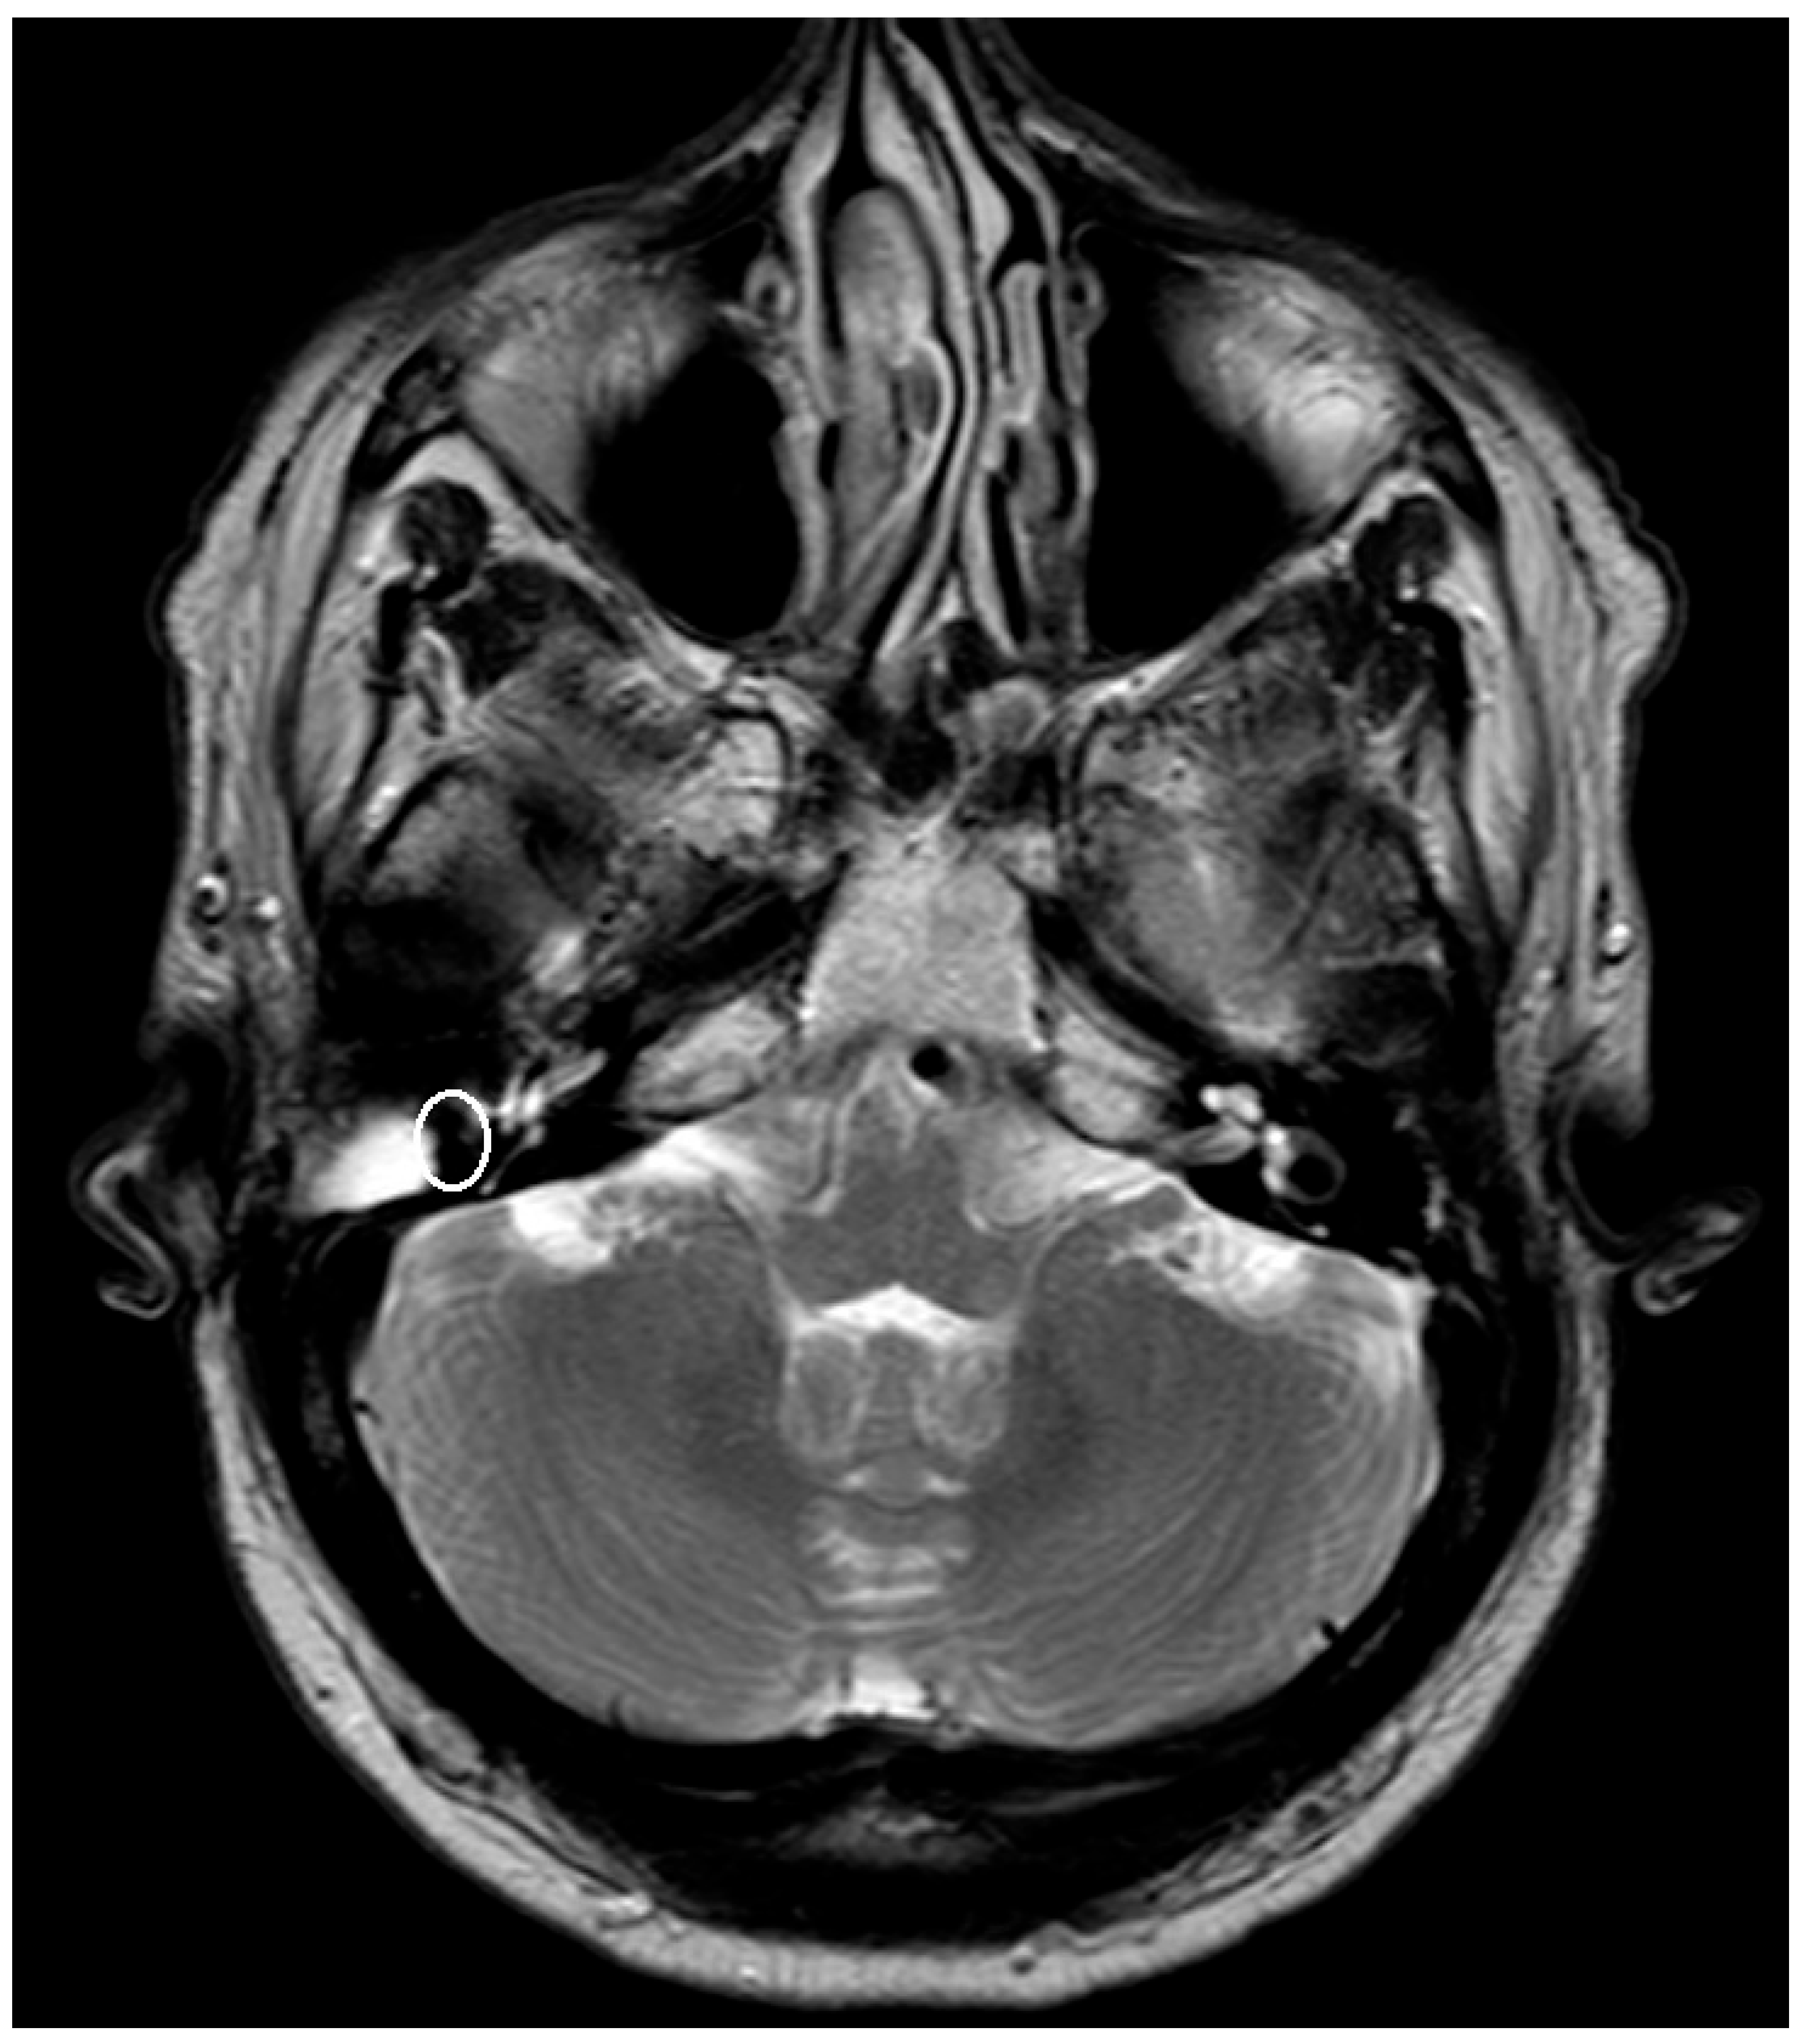

Figure 1. T1 fat-suppressed-Sequence post Gadolinium with artifact after implantation of a titanium mesh at the left-sided skull base, see white ellipsis.

An artifact was detected in all MRI examinations (see Figure 1, Figure 2 and Figure 3).

The artifact measurements firstly done in T1- or T2-sequence showed an average artifact of 3,1 mm for PORP, 4,7 mm for TORP and 3,6 mm for meshes (see Figure 4, Figure 5 and Figure 6). The overall average artifact was 3,8 mm.